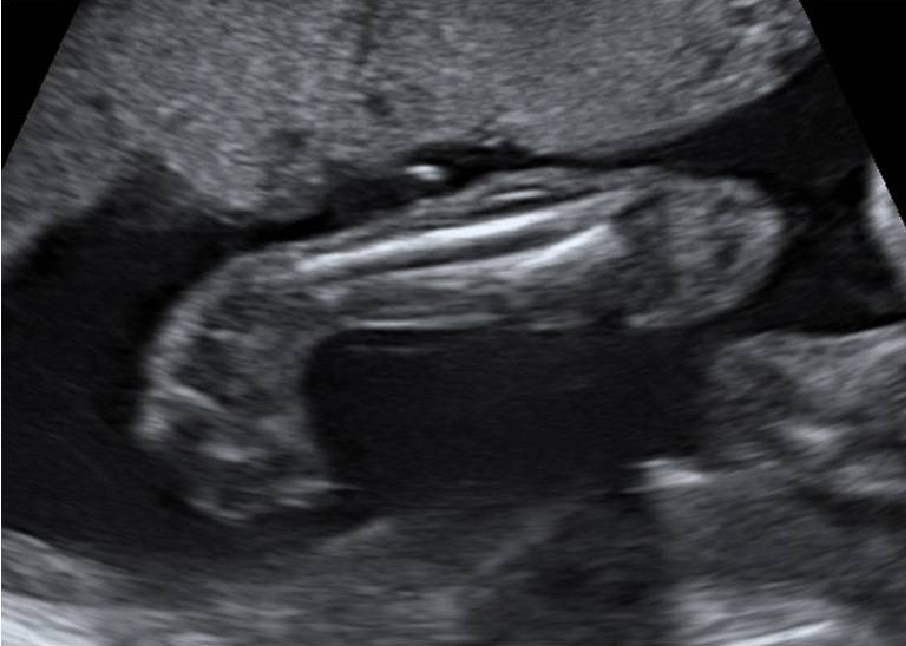

Le cause non sono ancora completamente conosciute, si pensa ad un’alterazione con attivazione dei geni responsabili della malattia che agisce durante la 12-16esima settimana di vita fetale (o di gravidanza). La diagnosi può essere fatta già in gravidanza attraverso l’esame ecografica. Ciò consente un adeguata informazione sulla patologia e sulle possibilità terapeutiche, nonché un trattamento precoce e adeguato che, se condotto da mani esperte evita il rischio di recidive.

Fig. 2 Foto piede torto in ecografia pre-natale